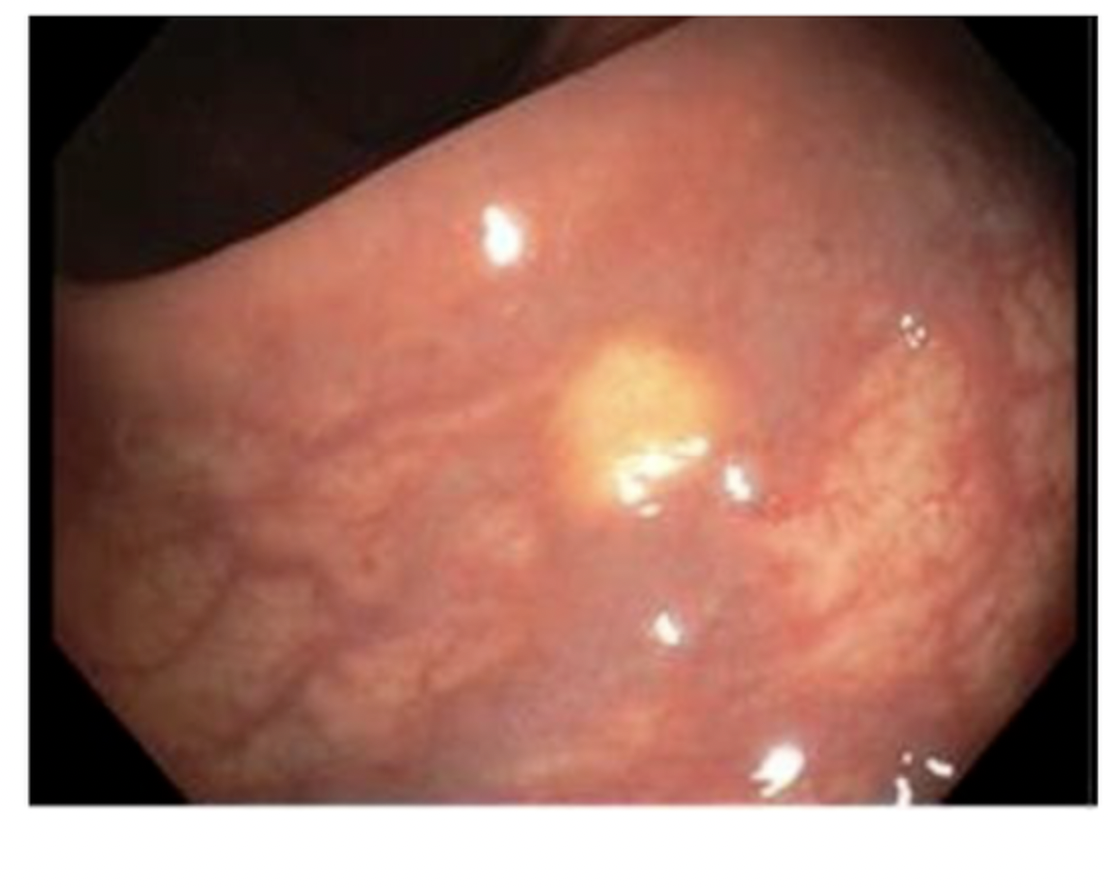

Seen in the rectum

A

rectal NET

if <1cm remove with polypectomy